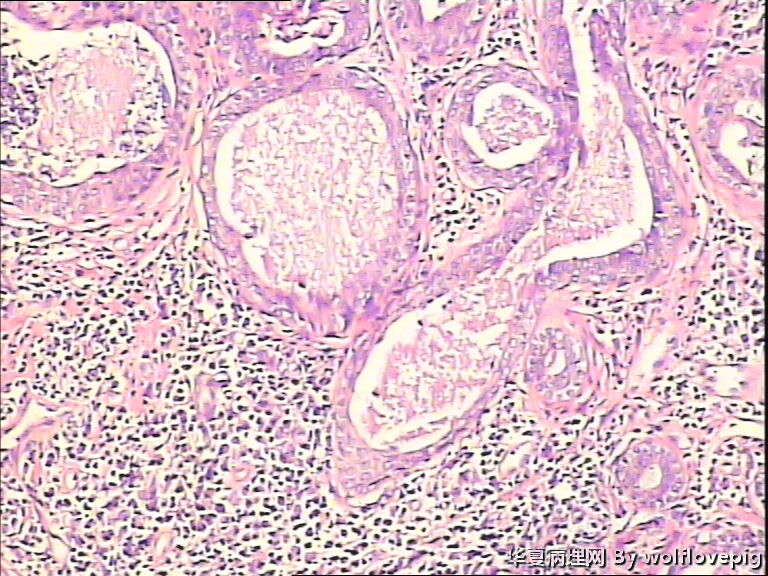

男,38y,腹部皮肤硬节20年。灰白不整形带皮组织一块:3.0*1.5*1.4cm,皮肤表面可见多个小结节样隆起。

图1